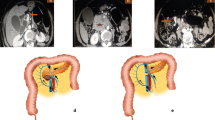

Types of vein resection and reconstruction according to the ISGPS [2] are presented in Fig. 1.

Types of vein resection and reconstruction according to the International Study Group of Pancreatic Surgery. a. Type 1 resection (small side-wall resection with direct repair); b. Type 2 resection (larger side-wall resection with patch repair); c. Type 3 resection (segmental resection with direct repair); d. Type 4 resection (segmental resection; an interposition graft is used for vascular repair)

Dissection proceeds following the technique recently reported for the “cold” triangle RPD [20]. The specimen is therefore mobilized from all retroperitoneal attachments, but the area of suspected vein involvement, by proceeding along the adventitial plane of large peripancreatic arteries (Figs. 3 and 4). At this time the surgeon has to decide which type of vein resection and reconstruction to perform.

Considering that two anastomoses are required, in type 4 vein resection and reconstruction initially only the SMV is crossclamped to maintain some portal flow through the splenic vein. Actually, if the inferior mesenteric vein drains into the splenic vein, also some venous outflow from the intestine may be maintained (Fig. 9). Once everything is ready for reconstruction the interposition graft is inserted into the abdomen. A suture is placed at the distal margin of conduit to facilitate graft orientation and handling. The anastomosis between the SMV and the interposition graft is performed first, using two half-running sutures as described for type 3 vein reconstruction. Next, splenic and portal veins are crossclamped, the SMV is divided near the spleno-mesenteric junction, the graft is trimmed at the appropriate length, and the second anastomosis is fashioned using the same technique described above (Fig. 10) (video 4).

Type 4 vein resection and reconstruction. When resection involves the proximal portion of the superior mesenteric vein, portal flow can be maintained through the splenic vein (arrows). From Boggi U (Ed.) Minimally Invasive Surgery of the Pancreas. Springer-Verlag Italia s.r.l. 2018 – https://doi.org/10.1007/978-88-470-3958-2